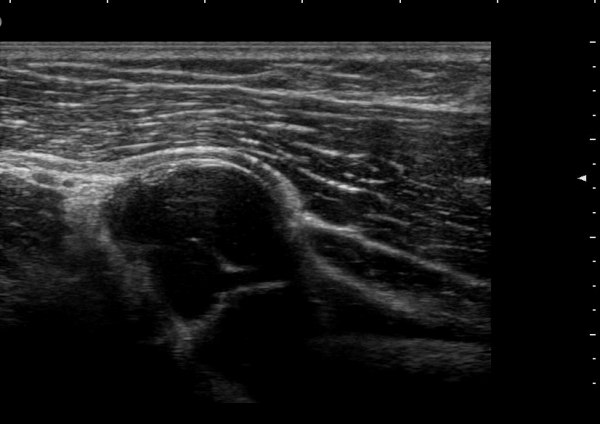

ÃÊÀ½ÆÄ °Ë»ç

¿ä°ñ½Å°æÀÇ Èİñ°£½Å°æºÐÁö Ⱦ´Ü¸é°Ë»ç¿¡¼­ ¼ÒµÎ Ç¥Ãþ »ó¿Ï±Ù°ú »ó¿Ï¿ä°ñ±Ù »çÀÌ¿¡¼­

½Å°æ ºÐÁö°¡ Àß °üÂûµÈ´Ù(±×¸² 1).